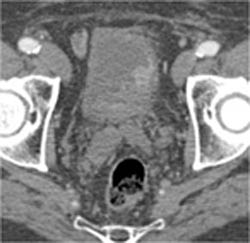

Diagnosis

Significant Coronary Artery Disease